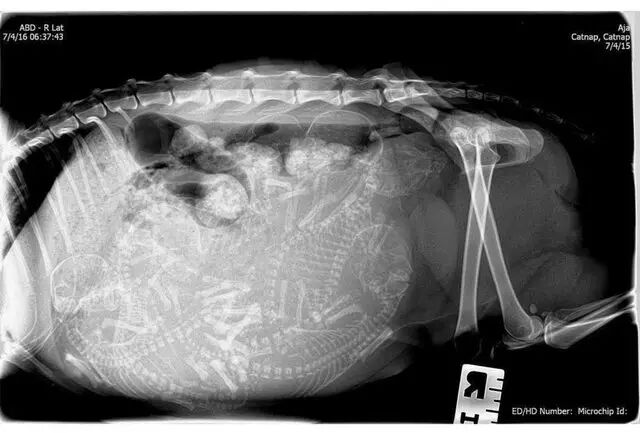

怀孕是一件神圣而又带有神秘色彩的事,她预示着新生命的来临。在动物世界,怀孕是怎样的一种奇迹,以下 14 种动物在怀孕期间的 X 线图片,我们可以通过全新的影像视角探查一番。

• 乌龟